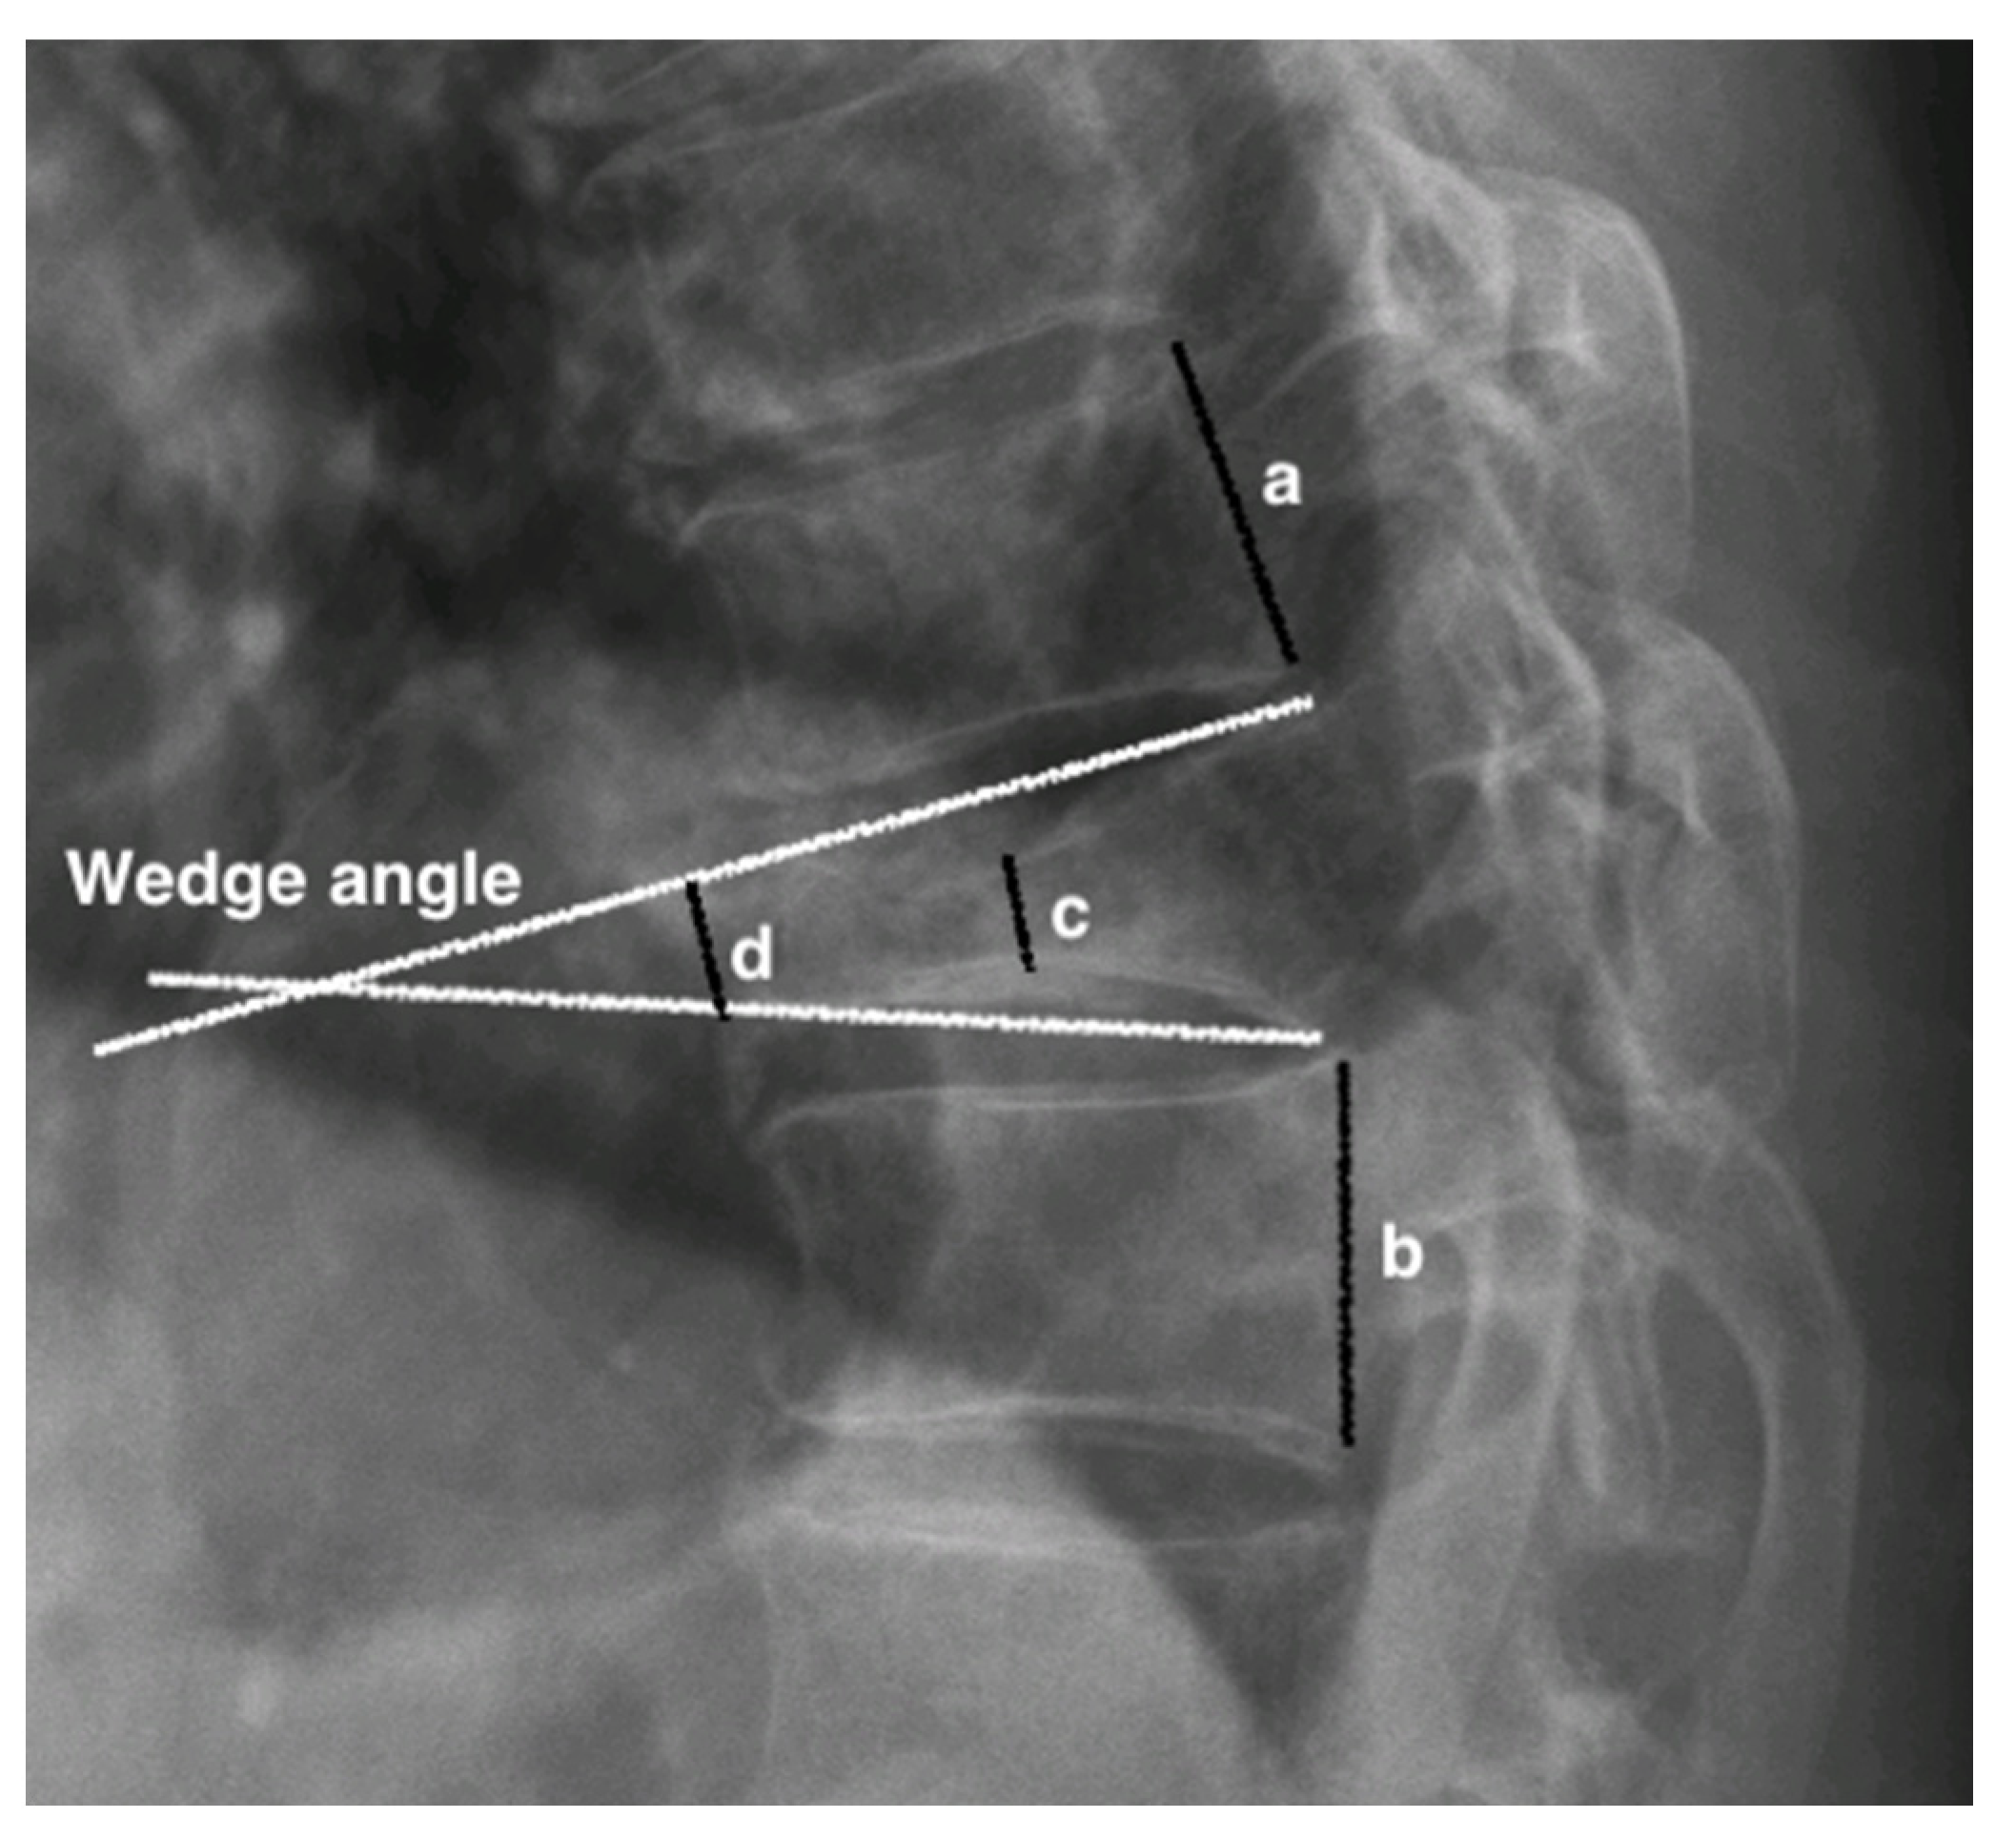

2.2. Measurement of Vertebral Parameters and New Bone Formation